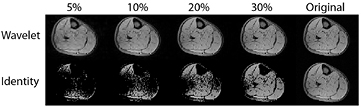

How then to explain how image acquisition can be accelerated by compressed sensing? First, let us imagine taking a picture with our digital camera. The sensors within the camera detect an image and signal intensity values are assigned to each of, say, 15 megapixels. However, storing the information for every pixel independently will lead to extremely large files, and so the camera instead mathematically converts the image to JPEG format (Taubman and Marcellin 2002). The JPEG 2000 format uses a mathematical transform known as a discrete wavelet transform to compress the information for storage at a smaller size. The discrete wavelet transform applies a nested series of low and high pass filters to the image, producing a wavelet space of the same matrix size as the original image space (Xiong and Ramchandran 2009). This property becomes most apparent if we examine the discrete wavelet transform of an MRI cross-section through the lower leg (figure 4(a)). Most of the pixels in the original image have non-zero signal intensity: the image is therefore not sparse. Some MR images are naturally sparse, such as angiograms, though the majority are not. It becomes sparse in the wavelet domain, since a smaller number of pixels (which are now wavelet coefficients) carry the important image content (figure 4(b)). The difference can be illustrated by ordering the image intensities and wavelet coefficients in order of absolute size (figure 4(c)). The image can be reconstructed with high fidelity from only the most significant coefficients in the wavelet domain, whereas this is not possible in the original image domain (figure 5). For real image objects, this is not a lossless compression, that is to say that the original data is not perfectly reconstructable from the reduced number of coefficients. Therefore, there will be a trade-off between the reduction in the number of wavelet coefficients used and the image fidelity required.

Figure 4. (a) Most MR images are not themselves sparse. In the image space, most of the pixels in the image contain important non-zero information. (b) Under the discrete wavelet transform, a lot of the important signal information has been compressed into a smaller number of pixels or wavelet coefficients with non-zero values, and there are many pixels with zero or near zero values. (c) If we put the absolute intensity values of the image intensity (green) and the wavelet coefficients (blue) in order we can see that the intensity of the wavelet coefficients tends towards zero much more rapidly. The wavelet representation is therefore sparse.

Download figure:

Standard image High-resolution imageFigure 5. Reconstructing images from a smaller number of coefficients. We take the intensity of the signal in the wavelet domain (top) or the image intensity (bottom) and retain only the highest intensity 5%, 10%, 20%, 30% of the signals. The remaining wavelets are retransformed to the image space. We can see that the wavelet space is much sparser than the original image space, with reconstruction from only 20% of the wavelet coefficients giving reasonable image definition compared to the original (right).

Download figure:

Standard image High-resolution imageSo how can we move from an issue of image storage to actually reducing the acquisition time? If we are able to describe an MR image in a transform space in which it is sparse, then the compressed sensing theory argues that we may be able to reconstruct that image from a smaller number of measurements in k-space, provided that the k-space undersampling is performed in such a way that the artefacts in the image domain do not give rise to structured aliasing. This is a direct contrast with the sampling patterns required for conventional parallel imaging (section 2.2 and figure 1(c)), which are regular undersampling patterns and give rise to structured aliasing of the signal under inverse Fourier transform.